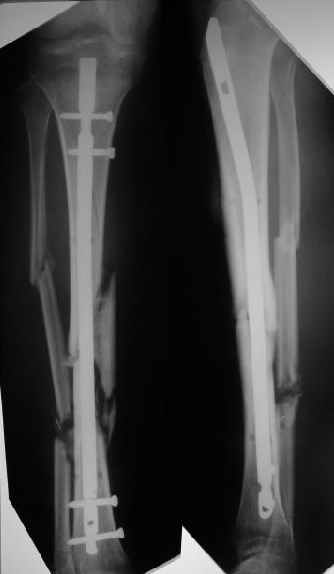

Наконец, 23 марта сделали и голень.